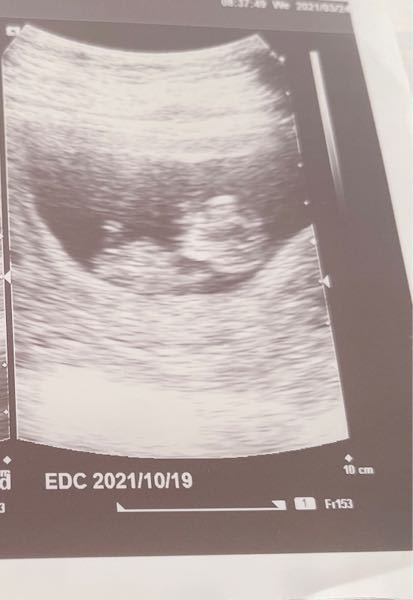

妊娠36週目 36w1d 4d のエコー写真とエピソード 妊娠10ヶ月 Cozre コズレ 子育てマガジン

妊娠36週目 胎児の体重 エコー写真 出産がもし始まったら 妊娠後期 All About

ダウン症の可能性はエコー写真からわかる! エコー写真ではダウン症かどうか100%判断できません。 しかし、ダウン症の可能性があるかは判断できます。 不安になる必要はありませんが、「もしかしたらそうなのかも」と心構えがしやすくなりますよね。 · 妊娠36週目(36w)のエコー写真を見ると、胎児の大きさはCRL(頭殿長)が47~48cm、体重は00~2900gほどに成長し成熟児に。 母体は、赤ちゃんと共に子宮が下がり食欲も戻って少し楽になります。 妊娠三十六週に万が一出産(=早産)となっても新生児医療の対象となる週数で、医療の助けで障害なく生存できる可能性が高いです。 前駆陣痛が始まる人もいる · 36週 エコー ダウン症 週数による平均的な大きさ エコー検査では主に、週数による平均的な身長等の大きさを調べますね。 性別の判明もエコーで分かりますが、妊娠5〜6ヶ月あたりに、胎児の向きで判別できます。